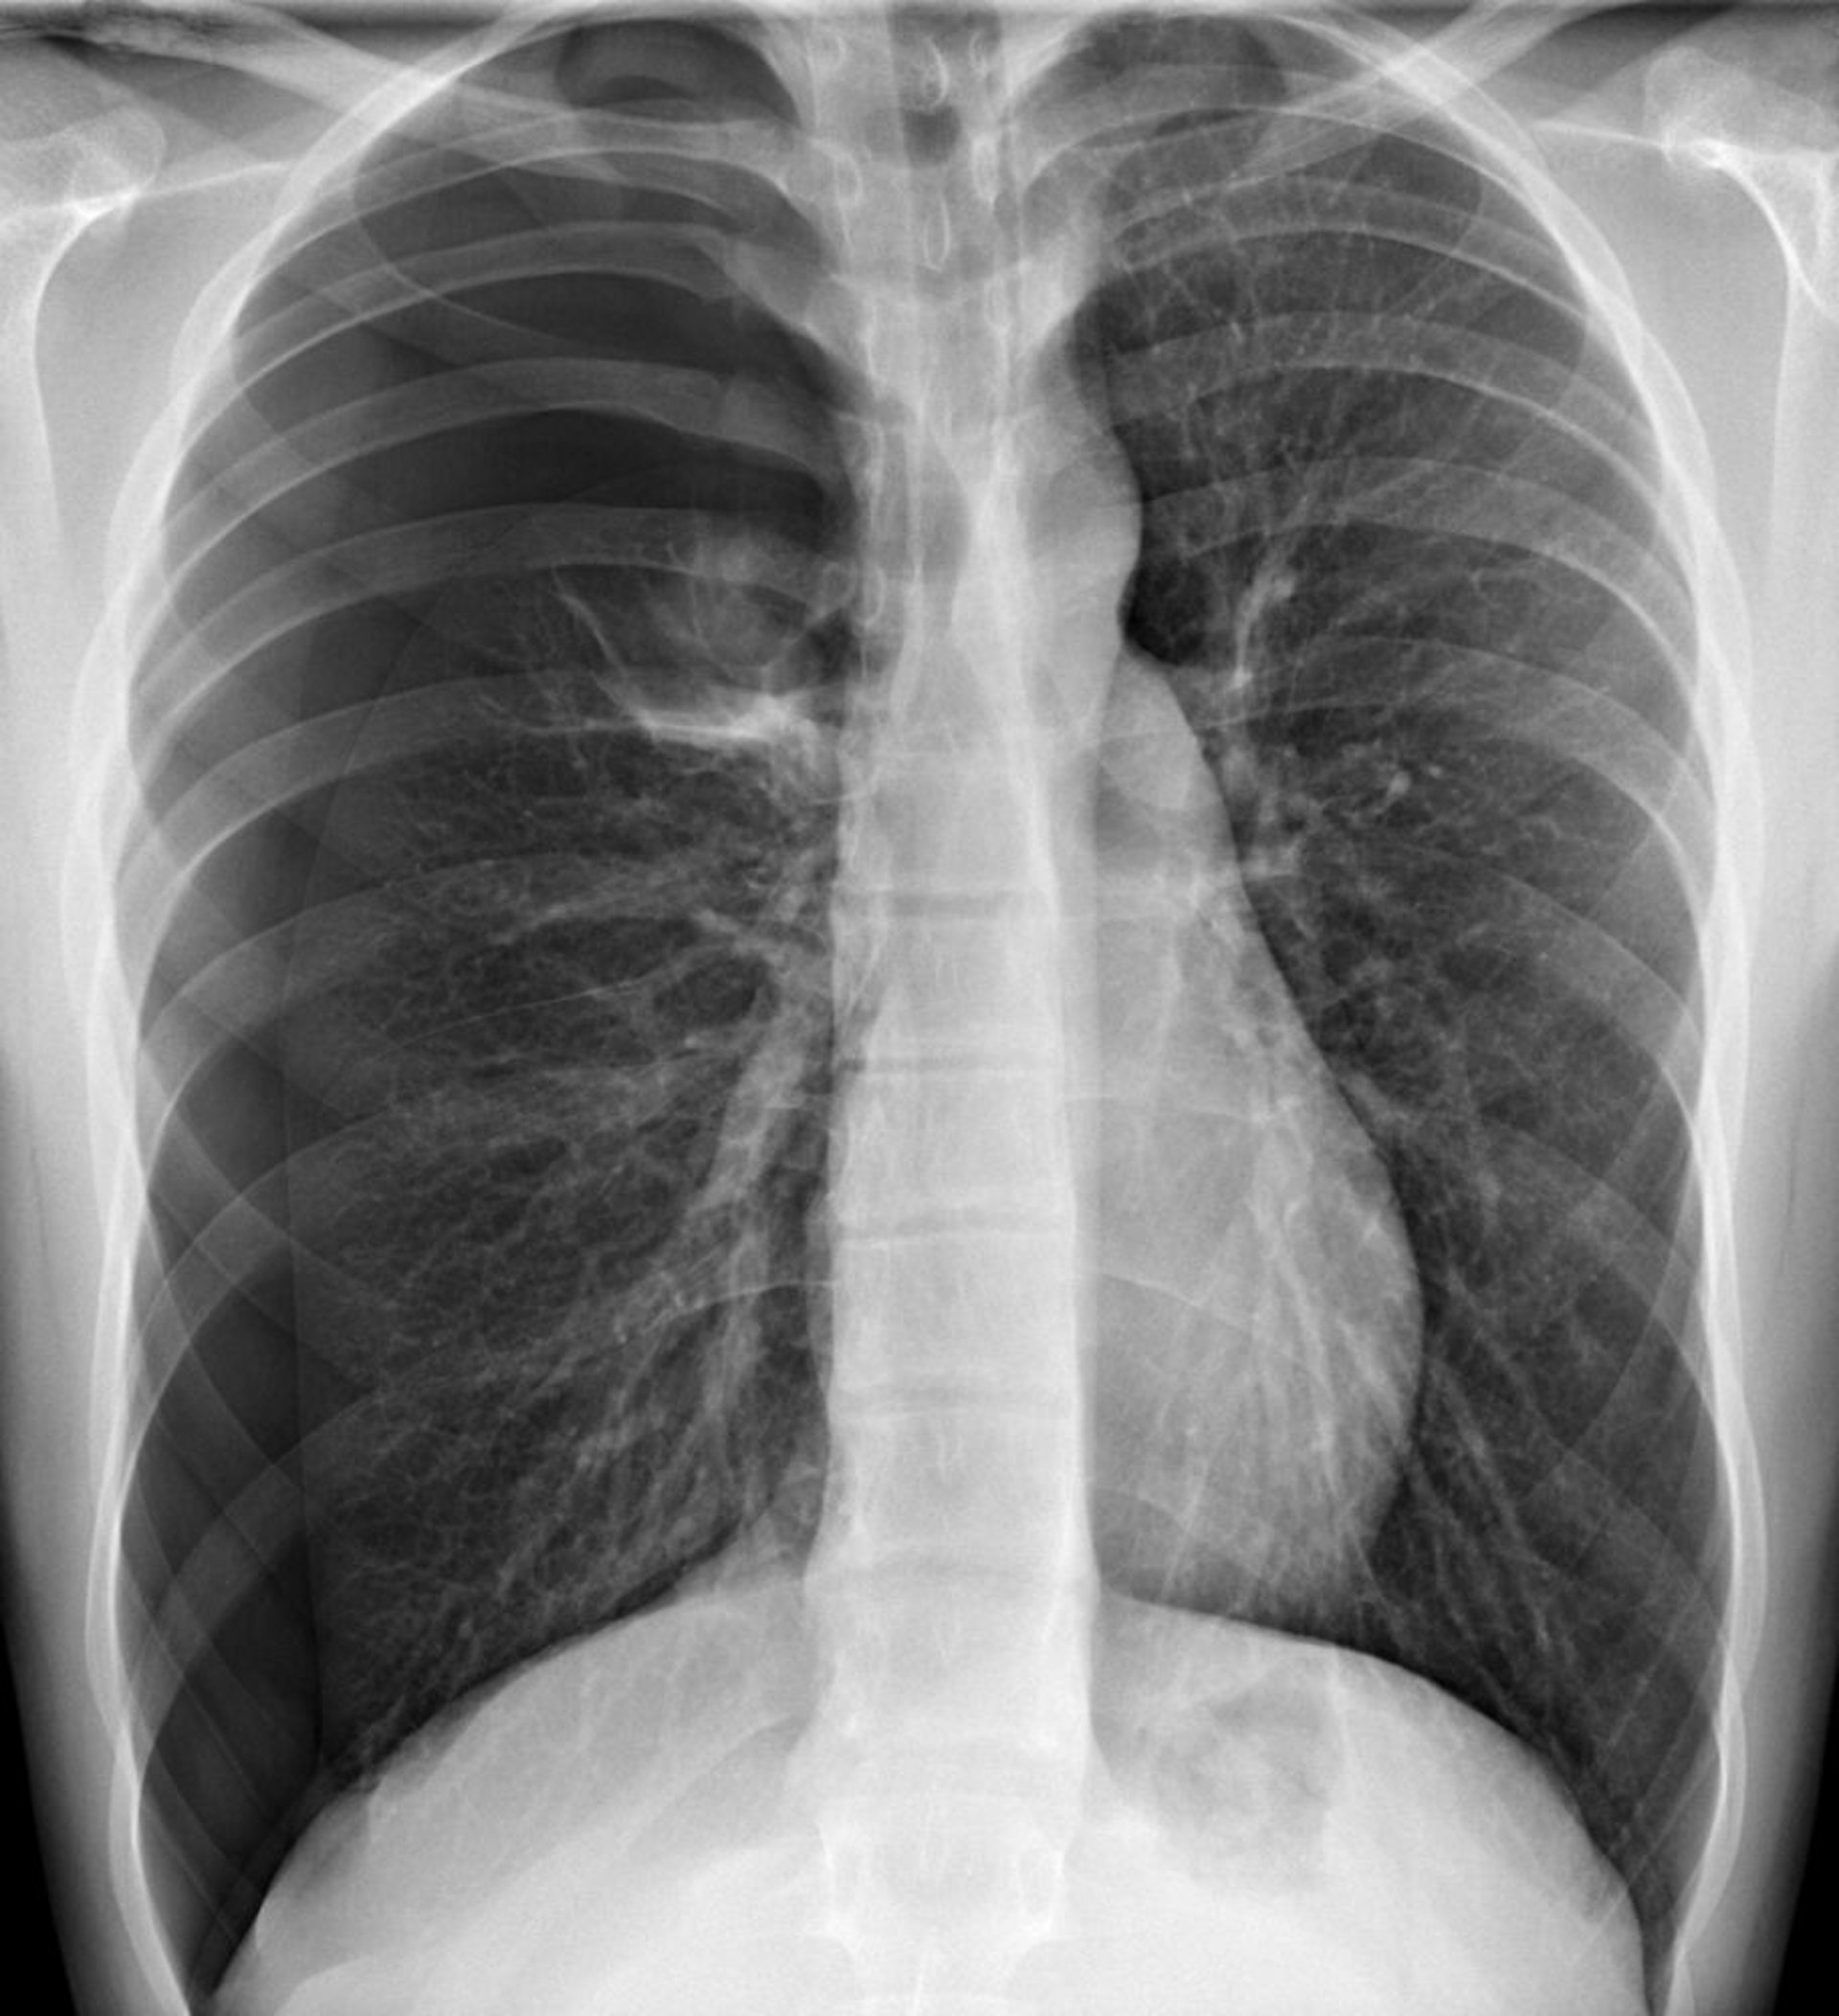

Neumotórax a tensión

En esta imagen, se ve un neumotórax en el hemitórax derecho, donde, en la periferia, no hay trama pulmonar. Un desplazamiento del corazón y el mediastino hacia el lado izquierdo puede causar fisiología del neumotórax a tensión. Sin embargo, el neumotórax a tensión debe diagnosticarse clínicamente y no esperar la confirmación radiológica.

DU CANE MEDICAL IMAGING LTD/SCIENCE PHOTO LIBRARY